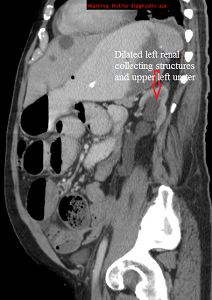

Prestenting AP CT_sagittal

Published July 13, 2014 at 212 × 300 in Internal stenting of the left ureter Ken U. Ekechukwu, MD, MPH, FACP..

Sagittal CT abdomen and pelvis showing dilated left ureter and calyces